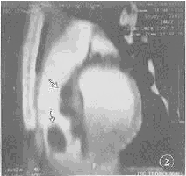

图1 病例1,室间隔右室侧与右室前壁间分叶状低密度占位(

)广泛交织,无边界,脂肪细胞核小,位于周边,未见异型性。病理:浸润性脂肪瘤。(HE×150)图4 病例Ⅲ,扩大的左心房内源于后壁的分叶状占位(

手术证实的7例非粘液性良性肿瘤,包括2例浸润性脂肪瘤,1例淋巴管瘤,2例纤维瘤,1例横纹肌瘤,1例二尖瓣前叶间皮瘤(见附表、附图1~8)。EBCT提示2例浸润性脂肪瘤为室壁或/和室间隔的壁在性占位,增强后CT值为-34~-101 HU;三维重建,可见瘤体起自心室壁推移冠脉或向心腔沿伸。2例纤维瘤起自左房后壁或室间隔,呈大分叶状或卵圆形,突向心腔,增强后CT值60~73 HU。横纹肌瘤1例,EBCT提示其起自于房、室间隔,呈多发结节状突向右心,强化后CT值约95 HU。淋巴管瘤1例亦为左室游离壁的壁在性肿瘤,增强后CT值为0~15.8 HU,该6例EBCT均提示较特征性的CT表现,结合临床均做出准确的组织病理学诊断,准确性为85.7%(6/7)。1例手术病理证实为二尖瓣前叶间皮瘤的病例,EBCT准确提示肿瘤位置、形状、大小与附着,因表现极似粘液瘤而定性为粘液瘤。2例术后复查同时提示胸腔积液与肺不张。

本组7例EBCT检查,在与超声心动图同样提示了心脏肿瘤位置、大小等方面征象的基础上,以不同的CT值提示了不同的病理学基础。如病例Ⅰ、Ⅱ瘤体增强后CT值仍为-34~-101 HU的脂肪密度而提示脂肪源性肿瘤,病例Ⅲ、Ⅳ瘤体CT值为60~73 HU,提示纤维实体肿瘤,病例Ⅴ、Ⅵ增强后CT值分别为平均95 HU的高密度及0~15.8 HU的水样密度,提示为血供丰富的横纹肌瘤与含水样物质的淋巴管瘤。病例Ⅰ、Ⅱ的EBCT三维重建,再现了肿瘤与心腔、心包或冠脉的空间关系。病例Ⅲ和病例Ⅴ的EBCT单层扫描同时显示了术后肺不张与胸腔积液。由于EBCT设备昂贵,国内外应用尚不普及,但其优越性将日益受到重视。

纤维瘤的发病率在儿童及成人非粘液瘤性肿瘤中分别居第二和第三位。男女发病率相似。左室游离壁前壁、室间隔好发,单发多见,瘤体呈卵圆形或分叶状,由成纤维细胞和纤维组织构成,质硬,表面光滑,少含血管,故CT值较高且无明显增强,瘤体中心血供较差,时见钙化[1,9]。笔者认为,起自室间隔或其它心壁的单发肿瘤,边缘光滑,EBCT值约60 HU左右且无明显增强,应首先考虑纤维瘤。